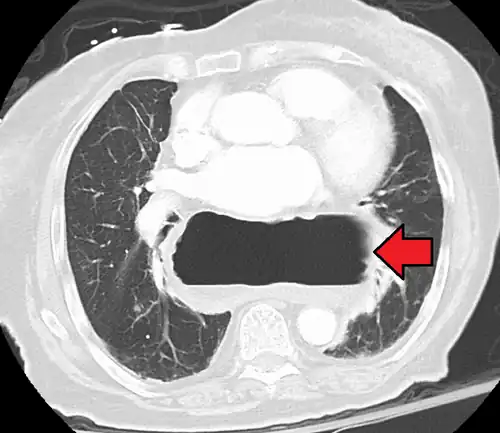

A hiatal hernia as seen on CT